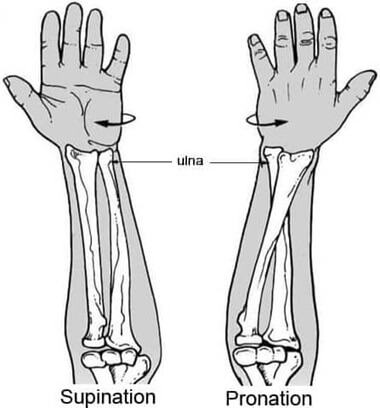

The distal part of the radius refers to the end nearest to your wrist. The radius is responsible for forearm rotation (turning your palm up and down) and supports the majority of the forces through the wrist joint.

The radius and ulna run parallel to each other when in a neutral position (supination) i.e. palm facing up, but when you twist your wrist so the palm faces down (pronation), the radius rotates to cross over the top of the ulna.

Both the radius and ulna are essential for the function and stability of the forearm and wrist.

Their coordinated movements enable actions such as flexion, extension, pronation, and supination of the forearm, contributing to the versatility and dexterity of the upper limb.